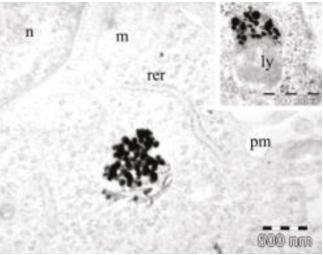

Fig. 8 Organul corti-prelevat de la animale-imagine de microscopie electronică

Fig. 9 Imagine de microscopie elecronică-se văd nanoparticulele de AgNO3 pătrunse în celulele de ureche internă recoltate de la animale viabile în culturi celulare

Fig.10 Imagine de microscopie elecronică-se văd nanoparticulele de AgNO3 pătrunse în celulele de ureche internă recoltate de la animale viabile în culturi celulare

(Fig. 7, 8) S-au studiat anumite substanțe otoprotectoare pe celulele organului Corti, diferiți antioxidanți, iar mai recent posibilitatea utilizării nanomaterialelor de Au și Ag folosite ca și vectori pentru anumite substanțe terapeutice, având ca țintă celulele urechii interne.

(Fig. 9) Toate aceste proiecte de cercetare au putut fi finalizate datorită echipei de cercetare multidisciplinare pe care am constituit o cu alte departamente din cadrul facultății noastre, precum și cu